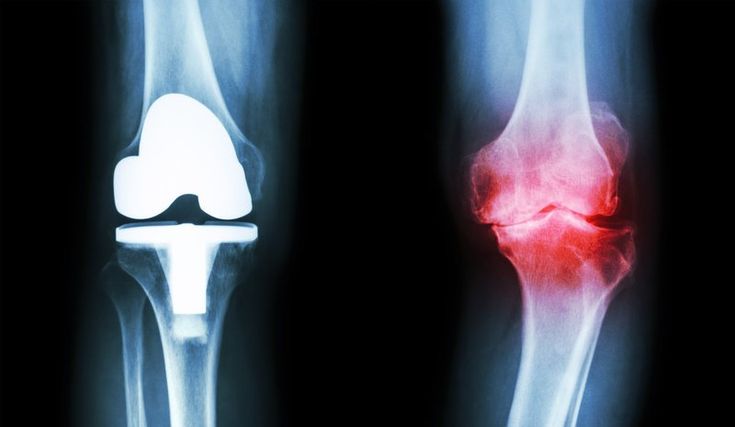

При рентгенологическом исследовании коленного сустава наблюдаем за состоянием бедренной кости, костных структур большеберцовой и малоберцовой костей, суставных поверхностей, шириной, интенсивностью рентгенологической суставной щели, формой и целостностью межсуставных возвышений. При исследовании можно выявить такие заболевания, как доброкачественные и злокачественные новообразования костей, деформирующие остеоартрозы, ревматические поражения суставов, кальцификации мягких тканей, прилегающих к суставу, положение протезов в протезированных суставах и т. д.